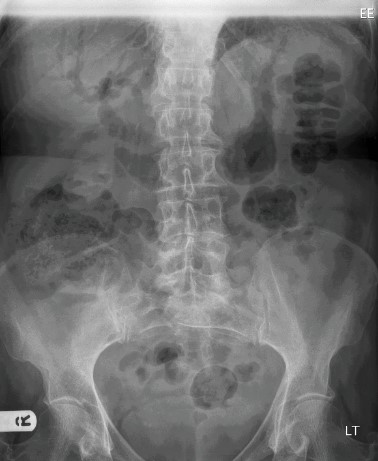

Pneumobilia

Also known as aerobilia. Accumulation of gas in the biliary tree. Seen as linear branching gas within liver most prominent in central large caliber ducts as the flow of bile pushes gas toward the hilum. Gas within the biliary tree tends to be more central, whereas gas within the portal venous system tends to be peripheral (carried along by the blood). Also, biliary gas is anti-dependent, and typically fills the left lobe of the liver.

“Saber sign”: Supine radiographs often demonstrate a sword-shaped lucency in the right paraspinal region representing gas from the common duct and the left hepatic duct. Present in ~50% of patients with pneumobilia.